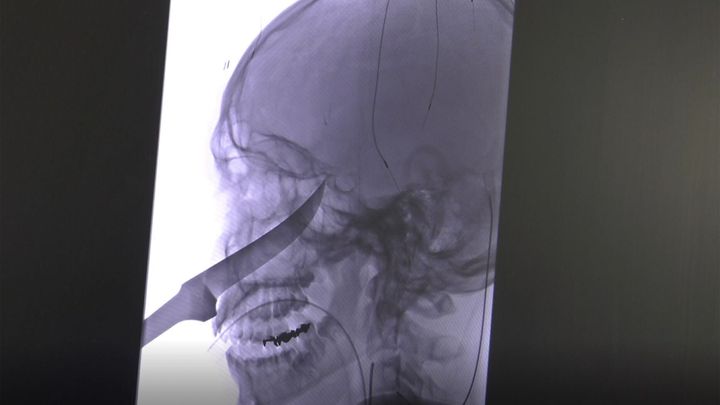

Miracol! A supraviețuit cu un cuțit de 25 de cm înfipt în față!

Un puști de 15 ani din Kansas, SUA, a reușit să își înfigă un cuțit de 25 de centimetri în față în timp ce se juca cu un grup de...